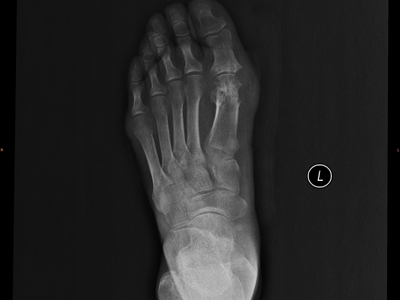

痛风是由于嘌呤代谢紊乱和尿酸排出减少,而引起的尿酸盐结晶沉积性病变,可累及指关节、第一跖趾关节、耳廓等处,造成急性炎症反应性滑膜炎。常于中老年发病,男性发病率明显高于女性,以皮下出现痛风石、痛风性关节炎、关节畸形、肾结石或肾脏病变为临床特征。痛风治疗原则为治疗高尿酸血症和控制关节炎。

痛风病程较长,常反复发作而迁延不愈形成痛风石,是痛风的特征性临床表现,常见于指关节、第一跖趾关节、耳廓等处。外观为隆起、大小不一的不规则的黄白色赘生物,表面菲薄,破溃后排出白色粉状或糊状尿酸盐结晶物,经久不愈,但较少继发感染。部分患者伴有肾结石及肾脏病变。